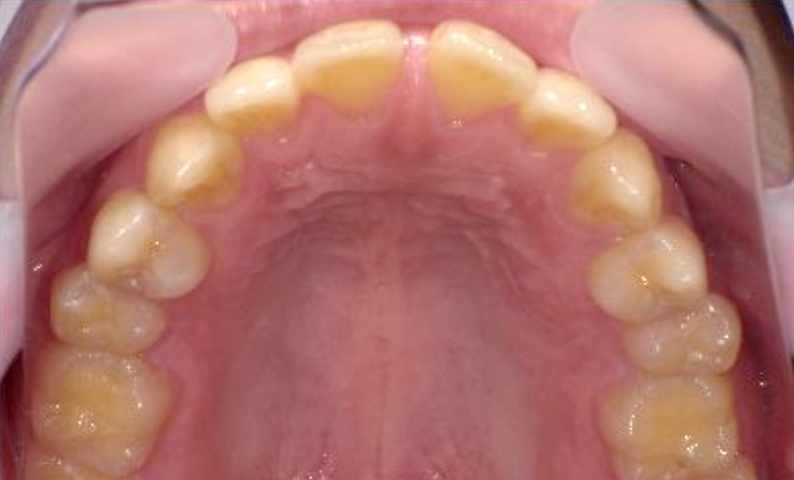

| 治療前 | 治療後 |

|---|---|

|